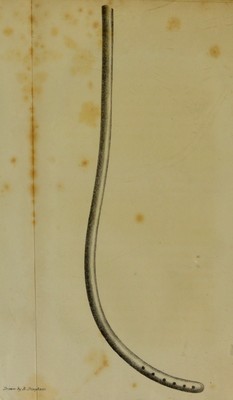

A practical essay on disease and injuries of the bladder : being that to which the Royal College of Surgeons adjudged the Jacksonian Prize for the year 1821 ... / by Robert Bingham.

- Bingham, Robert.

- 1822

Credit: A practical essay on disease and injuries of the bladder : being that to which the Royal College of Surgeons adjudged the Jacksonian Prize for the year 1821 ... / by Robert Bingham. Source: Wellcome Collection.